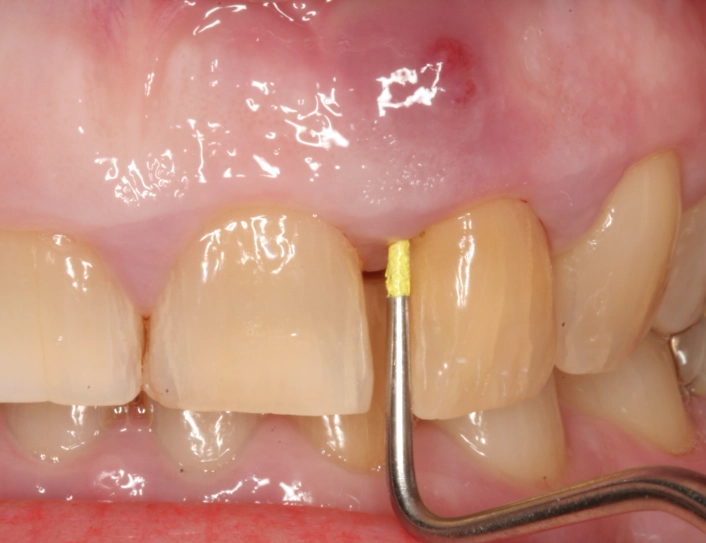

- Swelling in the Gums: Look in the mirror. Is there a pimple-like bump on the gum near the root of the painful tooth? Dentists call this a "parulis" or gum boil. It might be red, yellow at the tip, and it could ooze pus or blood if you press on it (though I don't recommend pressing on it). This is actually a drainage point for the abscess.

- Address Dental Trauma Immediately: If you chip or knock a tooth, see a dentist even if it doesn't hurt. The nerve can be damaged and die quietly, leading to an abscess months or years later.